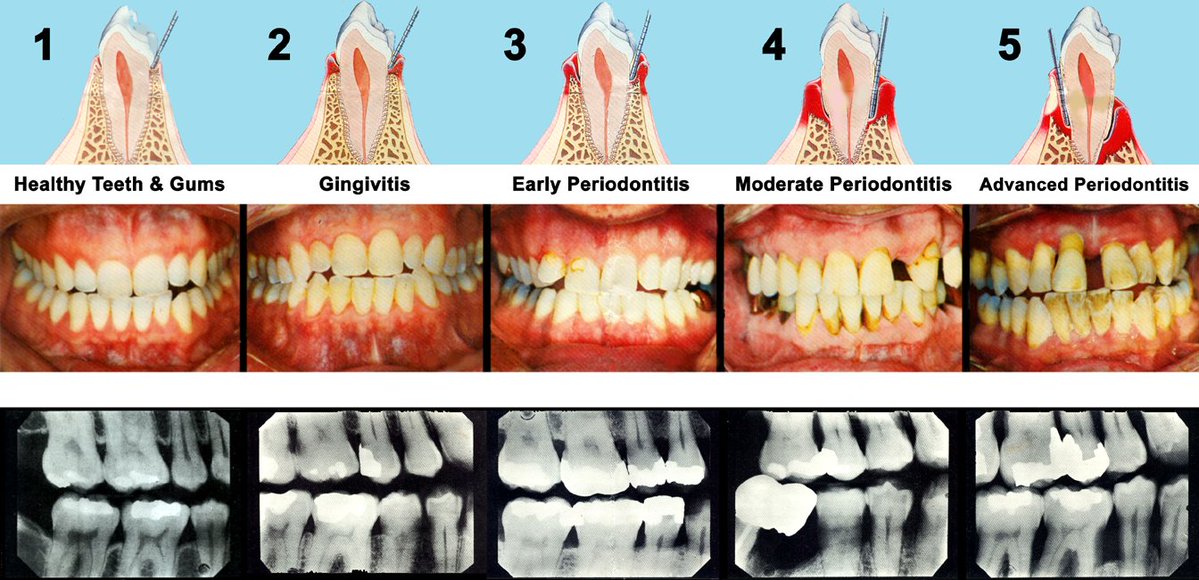

Polysorbate 80 and carboxymethylcellulose are absolutely ubiquitous in foods and supplements.

In rodent studies, these emulsifiers cause dysbiotic bacterial overgrowth and support the genesis of COLITIS, i.e inflammatory bowel disease.Image

Specifically, Polysorbate 80 and carboxymethylcellulose seem to foster an environment ripe for mucus-degrading bacteria, degrading this layer of critical protection and paving the way for conditions like colitis and metabolic syndrome in animals.